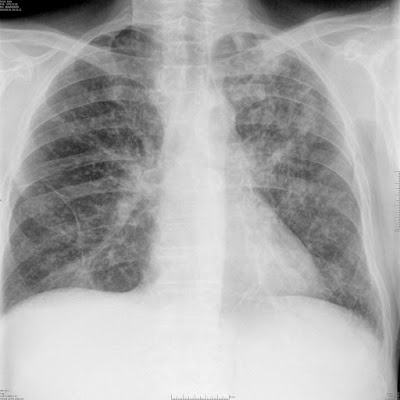

Miliáris árnyékok bilaterálisan, régebbi gyulladás maradványa a bal tüdőcsúcsban